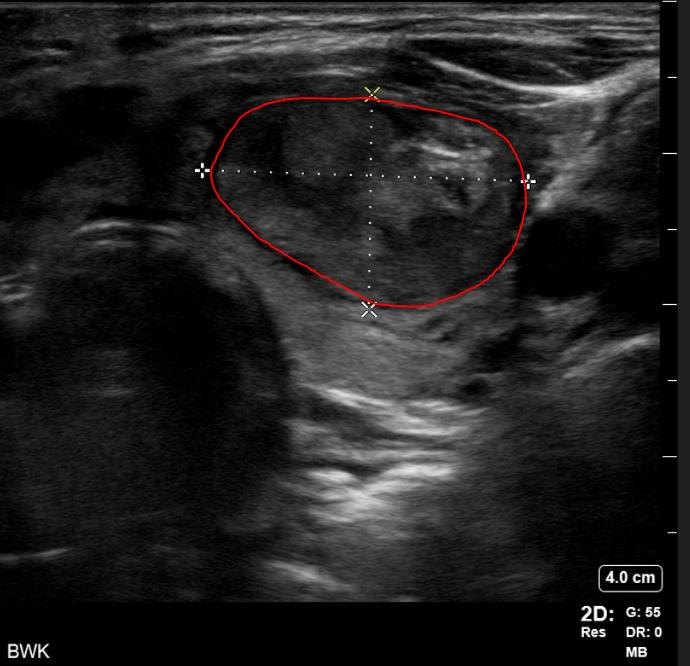

During her physical exam, I noticed the patient had a protuberant thyroid on the left side of her neck, causing cosmetic deformity and easily visible in any neck position. Ultrasound imaging confirmed the patient had multiple

thyroid nodules. She had no overt manifestations of thyrotoxicosis such as tremor, tachycardia, flushing or diaphoresis. She had no evidence of thyroid eye disease or exophthalmos. She was otherwise well appearing with a normal neurological examination.

Thyroid Ultrasound

The right lobe was heterogeneous with parenchymal hypervascularity, measuring 4.9 x 1.5 x 1.1 cm. There were three nodules present, all of them less than a centimeter in size. None of the nodules had highly suspicious features. The isthmus also had no significant nodules and was not thickened.

The left lobe was heterogeneous and measured 5.5 x 2.4 x 2.4 cm, with two notable nodules in her left thyroid lobe. There was a smaller mostly cystic nodule, which measured 2.2 x 2.1 x 2.2 cm. She also had a larger heterogeneous,

hypervascular solid nodule that contained internal microcalcification located in the left middle inferior lobe. This nodule measured 3.0 x 3.1 x 2.3 cm (calculated tumor volume = 11.3 mL).

When comparing the imaging to the nuclear medicine iodine scan, the dominant left solid hypervascular nodule appeared to correspond to the area of increased uptake on the thyroid scan, and clinically this was deemed most certainly the hot or toxic nodule.

Once the perithyroidal block was completed, the RFA electrode (the size equivalent of an 18-gauge needle) was inserted using ultrasound guidance into the known dominant toxic nodule on the left. Utilizing a transisthmic approach and the “moving shot” technique, I sequentially ablated the dominant left-sided nodule. A maximum of 40 watts was used via a 7 mm active tip electrode, with a total ablation time of about 20 minutes.

I monitored each segment of ablated nodule for hyperechoic “bubbling” visible on ultrasound, and for rising impedance from the electrode generator, to assure adequate ablation throughout. During the critical portion of the procedure, I asked the patient to vocalize to assure that no acute voice changes or hoarseness was observed. None were noted and the patient tolerated the procedure well. A bandage was placed over the needle site and the patient was observed for one hour prior to discharge home. Follow-up was arranged for set intervals (one, three, six and 12 months following the ablation) with ultrasound examination of the nodule and thyroid function lab testing.

Just a few months following the procedure, the patient had completely normal thyroid function restored and is doing very well. Her TSH returned to the normal range following the procedure (1.08)

and she reports that her hyperthyroid symptoms resolved. She feels like the nodule is reducing in size with less compression symptoms in her neck, and she has a more normal neck contour. Volumetric ultrasound analysis of her treated nodule at six months shows that her nodule is now less than 3 mL in volume, a 75% decrease in volume from pre-procedure baseline. Further, the procedure did not cause hypothyroidism necessitating thyroid hormone replacement, a known complication of both surgery and radioactive iodine.